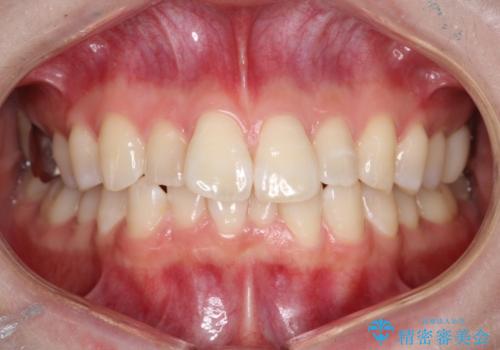

[ 総合歯科診療 ] がたつきの改善とセラミック治療

![[ 総合歯科診療 ] がたつきの改善とセラミック治療の症例 治療前](https://seimitsushinbi.jp/wp/wp-content/uploads/2024/03/f0f438a14c56b185411649f48b5b188c-500x350.jpg?v=1710833163)

![[ 総合歯科診療 ] がたつきの改善とセラミック治療の症例 治療後](https://seimitsushinbi.jp/wp/wp-content/uploads/2024/03/7212917eb9c4ef33050c52e7f9724490-500x350.jpg?v=1710833188)